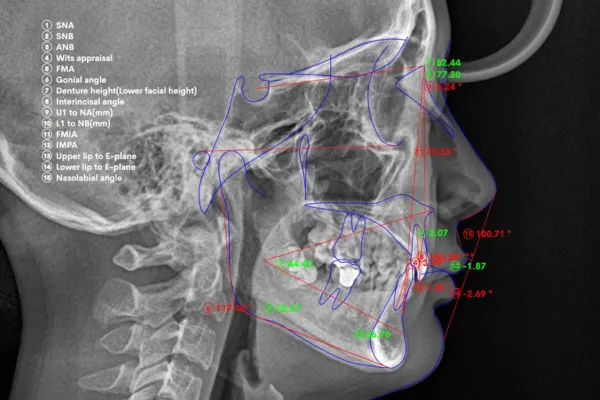

精密検査

セファロ分析で、歯並び・かみ合わせ・歯ぐきの状態をていねいに確認します。